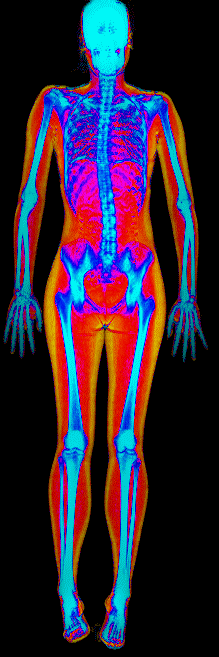

What Fat Loss Looks Like on a DEXA Scan

Red = muscle, gold = fat, blue = bone.

Lost 26.0 lb of fat · 187 → 150 lb · Age 44

Lost 25.4 lb of fat, gained 3.7 lb lean · 201 → 180 lb · Age 33

Lost 24.9 lb of fat, gained 12.0 lb lean · 183 → 170 lb · Age 37